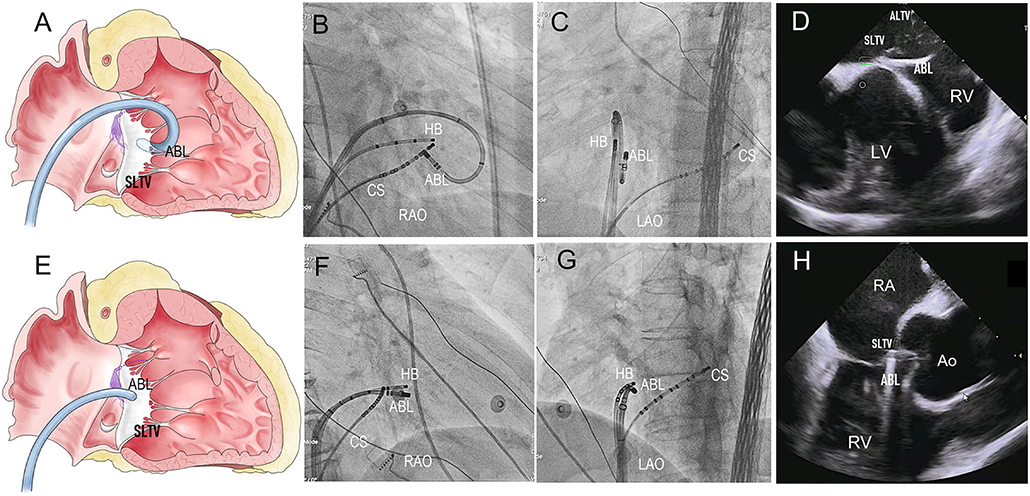

EP Mapping at the Preferential Regions

For right PHVAs, the B-SLTV region was preferentially mapped. To access to the subvalvular area, the ablation catheter was introduced to the right ventricle via a Swartz sheath (SR0 type, St. Jude Medical, MN, USA), then curved reversely and clockwise rotated the catheter and pulled it back toward the tricuspid annulus, to form catheter inversion configuration (Figures 2A–C). The position of the catheter tip was judged by fluoroscopy and confirmed by intracardiac echocardiography (ICE) imaging (CARTO Sound, Biosense Webster, CA, USA) (Figures 2D,H). For left PHVAs, the mapping catheter was advanced in the left ventricle via trans-aortic retrograde approach to map the left parahisian region and the septal region of mitral annulus (Figure 3).

Figure 2. The Catheter placement in the B-SLTV and A-SLTV approach. (A) The schematic diagram illustrating the catheter tip was reversely curved beneath the SLTV (RAO view). (B,C) The fluoroscopic images showing the catheter was reversely curved beneath the SLTV through a long sheath (RAO and LAO view). (D,H) The ultrasonic images confirmed the catheter placement beneath the SLTV. (E) The schematic diagram showing the catheter tip was directly placed above the SLTV (RAO view). (F,G) The fluoroscopic images showing the catheter tip was placed directly above the SLTV (RAO and LAO view). HB, the His bundle; CS, coronary sinus; ABL, the ablation catheter; SLTV, the septal leaflet of the tricuspid valve; ALTV, the anterior leaflet of the tricuspid valve; RA, the right atrium; RV, the right ventricle; LV, left ventricle; RAO, right anterior oblique; LAO, left anterior oblique.

Left PHVA Ablation

Sub-aortic valve ablation was successful in all seven patients with left PHVA. In each of 4 patients with failed right parahisian ablation, the V-QRS time at the left-sided target was greater than that at the right-sided target (27 vs. 24, 31 vs. 29, 16 vs. 14, 33 vs. 31 ms, respectively). Compared with right PHVA, left PHVA exhibited higher proportion of precordial transition ≤lead V2 and lower proportion of QS shape in lead V1 on ECG recordings (Table 2). The procedural parameters were comparable except that the target-HB distance was greater in left sided group than that in right-sided group.